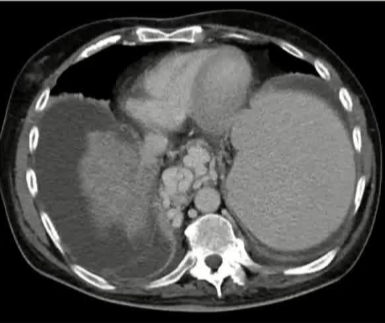

栓塞材料的可及性(例如病灶栓塞材料的可到达性)accessability (e.g. reachability of the nidus) 栓塞的预期深度intended deepness of embolization 如果需要让栓塞填满最后1mm 预期效果(例如:门静脉栓塞的炎症)intended effect (e.g. inflammation in PVE) 凝血状态(达到止血效果所需的时间)coagulation state (duration until hemostasis) 并发症(过敏、心律不齐、肺动脉高压、肝纤维化等)comorbidities (allergies, arrythmia, pulmonary hypertension, lung fibrosis etc.) 处于危险中的结构(包括下游部分-downstream和反流部分) structures at risk (downstream & backwash) 靶病变定位(浅层与深层) target lesion localization (superficial vs. deep) 不会选择一些会引起炎症的东西,因为那会病人来说真的很痛苦浅层病变 栓塞所需的速度(例如:危及生命的出血情况)required speed of embolization (e.g. life threatening hemorraghe) 院外专业人员(DSA技术人员和介入放射科医生)local expertise (technicians & IR's) 可用性与定价 availabilty & pricing Patient assessment for the choice of the ideal liquid emboli 影像学 62岁 男性

腹腔侧支循环

腹水 水肿 jaundice 男性乳腺发育症 多血管蜘蛛状结构(提示存在食管静脉曲张) 肝掌 (palmar erythema) 指表皮或真皮层受刺激后毛细血管扩张引发的局部皮肤发红现象 和患者说话